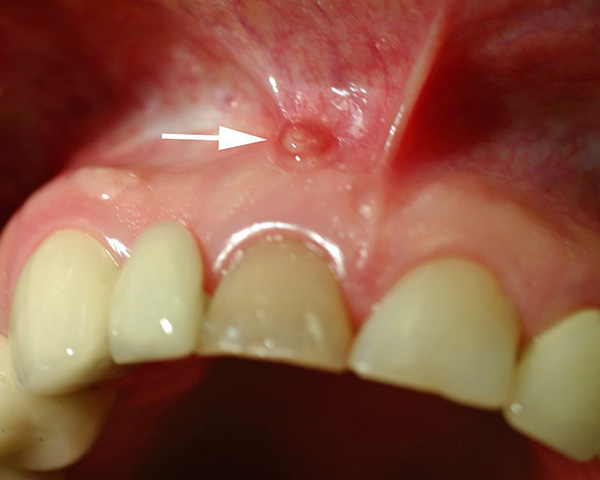

Também existem muitos exemplos em que a cárie não tratada em poucos meses passa para uma forma de pulpite, na qual o paciente pode literalmente tomar analgésicos, mas eles não o ajudam. E mesmo que a pulpite entre em periodontite, isso ainda não significa uma diminuição da dor. A periodontite geralmente é um processo purulento, quando a face se torna assimétrica e, na melhor das hipóteses, o pus é secretado na cavidade oral através da fístula;

A fotografia abaixo mostra uma fístula na gengiva acima do dente da frente “morto”:

É muito difícil conduzir anestesia para esses pacientes no local onde o exsudato purulento está localizado. Freqüentemente, várias abordagens precisam ser feitas para injetar pelo menos alguma solução anestésica, uma vez que a área próxima à raiz simplesmente não contém fisicamente o excesso de líquido. É por isso que vários dentistas são limitados à primeira consulta apenas com um corte ao longo da dobra de transição, para que, na próxima consulta, lide com condições mais confortáveis durante o tratamento (principalmente para o paciente).